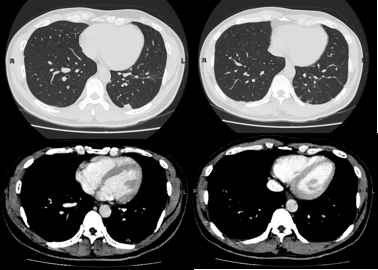

患者女,44岁,2013年CT发现左上肺结节,大小约9 mmx10 mm,伴右侧气胸。左上肺结节没有进行特殊处理。但因为患者反复出现右侧气胸。所以于2014年进行右侧肺大疱切除术,同时复查胸部CT示左上肺结节大小较前相仿。随后患者未定期复查。

2月前患者突发上腹部痉挛性疼痛,伴胸闷,查胸部CT示左上肺结节影较2014年增大(10 mmx15 mm),伴右侧液气胸,遂于2018年11月14日入我院。患者无特殊职业史,无吸烟史,无肺癌家族史。

我院CT提示患者右侧胸腔可见大量积气,右肺受压面积大于60%;右肺上叶见条状高密度影,边界清楚;左肺上叶尖后段见斑片状磨玻璃影(10 mmx15 mm) ,形态不规格,边缘见毛刺,内部血管走形紊乱、纤细,邻近胸膜牵拉。初步判断患者为左肺上叶尖后段磨玻璃密度病变,性质待定,不除外早期周围型肺癌可能。